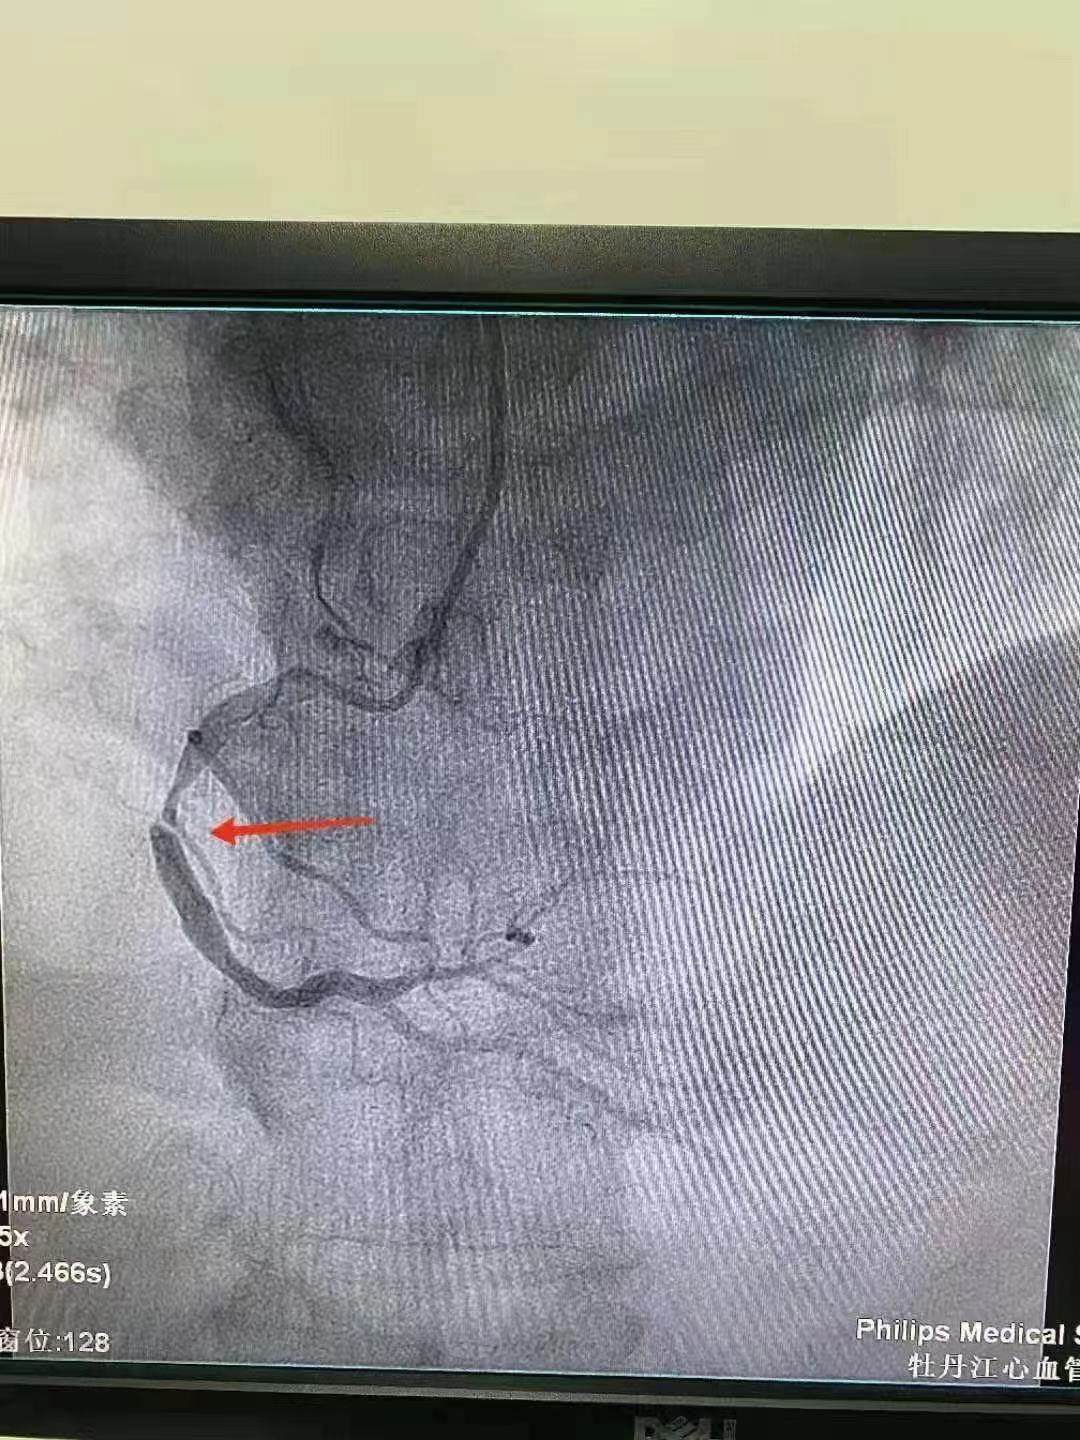

祝賀 牡丹江心血管病醫院關春普 主任團隊成功為患者植入Xinsorb生物可吸收支架!

祝賀 牡丹江心血管病醫院關春普 主任團隊成功為患者植入Xinsorb生物可吸收支架!

祝賀 牡丹江心血管病醫院關春普 主任團隊成功為患者植入Xinsorb生物可吸收支架!